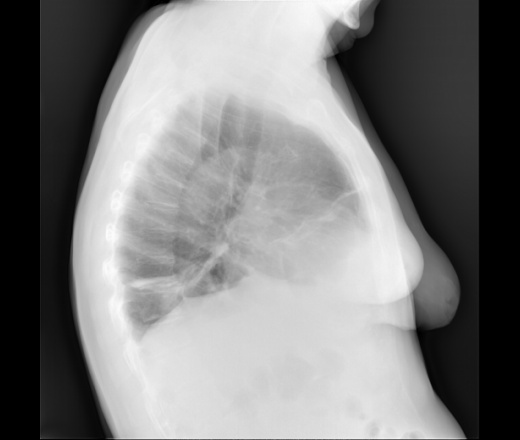

прямую досылаю проекцию

Синусы свободны, диафрагма уплощена. Справа не исключу реактивные субсегментарные ателектазы. Контроль в динамике.

С учетом того, что " 2 недели назад была температура" и " год назад не было фиброзных изменений" можно предположить в лучшем случае течение нижнедолевой 10сегмент пневмонии ( генез?) м.б. с некоторым уменьшением об' ема, в худшем случае обтурацию сегментарного бронха. О двухнедельном фиброзе говорить рано. Согласен " контроль в динамике".

Обозвал бы это дисковидными ателектазами.

А болевого синдром нет, со стороны органов грудной клетки или верхнего этажа брюшной полости? Правда, картина похожа на дисковидные ателектазы.